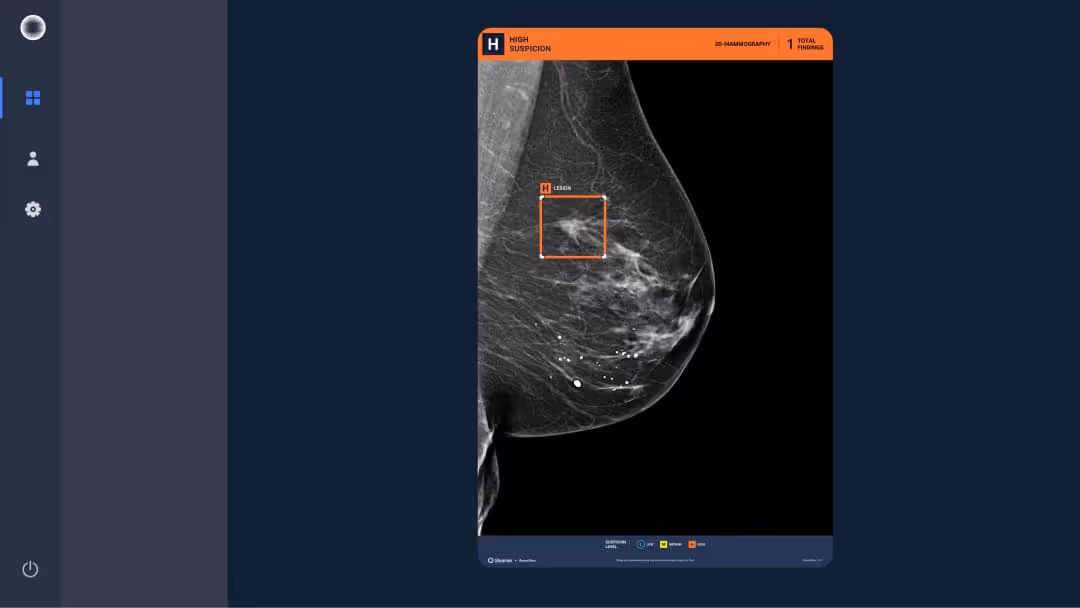

63 y.o. patient presenting as part of organized screening.

Results

BreastView detected a lesion that was a non-specific infiltrating carcinoma.